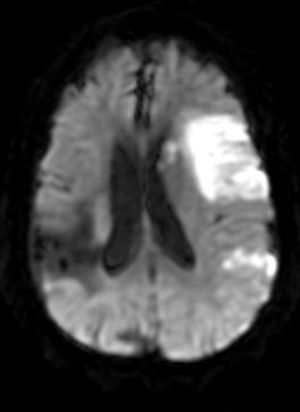

Take a look at these 3 images and see if you can pinpoint the cause of altered consciousness in this woman.

Published: August 8th 2014 | Updated: